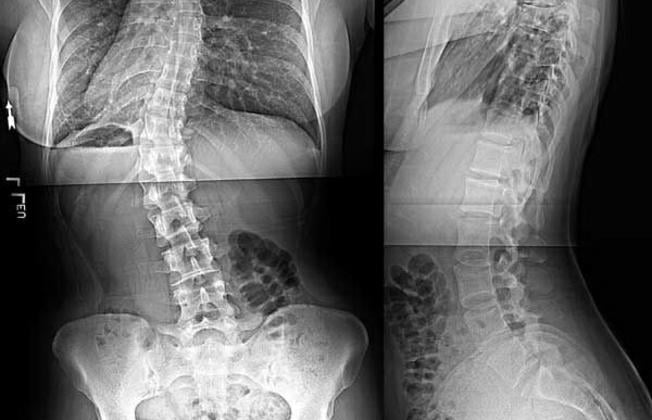

Strukturalna skolioza je složena deformacija kralježnice u frontalnoj, sagitalnoj i horizontalnoj ravnini s prisutnošću rotacije i torzije kralježaka. Skolioze nastaju zbog raznih etioloških čimbenika, a najčešći su: genetski (i to 8 puta češće nastaje u žena), metabolički faktori (metabolizam kolagena), faktori održavanja ravnoteže i rasta (gdje skolioza prati ubrzan tjelesni rast). Najčešća je idiopatska skolioza (čak 80 - 90 posto) što znači da je uzrok nepoznat. Idiopatske skolioze mogu se razviti tijekom cijelog djetinjstva i adolescencije, a najčešće nastaju tijekom razdoblja naglog rasta. Strukturalna skolioza se prema lokalizaciji dijeli na: cervikalnu, cerviko-torakalnu, torakalnu, torako-lumbalnu i lumbalnu. Dijeli se i prema stupnjevima po Cobbu: Laka je do 30 stupnjeva (preporučuje se asimetrično vježbanje, bavljenje aktivnosti poput plivanja); srednja je pod 30 do 50 stupnjeva Cobbovog kuta i zahtijeva iznimno vježbanje, no i uključenje steznika (Milwaukee) koji se nosi kako bi se i fizički djelovalo na ispravljanje kralježnice, i teška koja prelazi 50 stupnjeva po Cobbu i najčešće zahtijeva operativno liječenje.

Provodi se fizioterapijska procjena. U frontalnoj ravnini vidljiva je razlika lijevog i desnog ramena (jedno bude spušteno), asimetrija lopatica, razlika u Lorenzovim trokutima, nejednaka visina kukova, asimetrija prsa, rebrena grba. Moguća je i nejednakost donjih ekstremiteta. Testom pretklona se definitivno utvrđuje je li skolioza strukturalna skolioza. Pacijent se nagne prema naprijed u lagani pretklon. Ako deformacija kralježnice postoji i dalje, te je vidljiva grba (gibus), radi se o pravoj skoliozi.